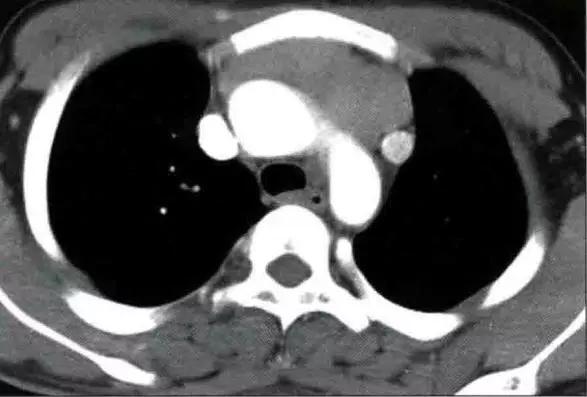

非侵袭性胸腺瘤CT图像

a. CT平扫示前上纵膈主动脉弓与胸骨间软组织密度肿块,密度均匀,边缘浅分叶状 b. CT增强示肿块均匀强化,肿块与主动脉弓之间脂肪间隙清晰